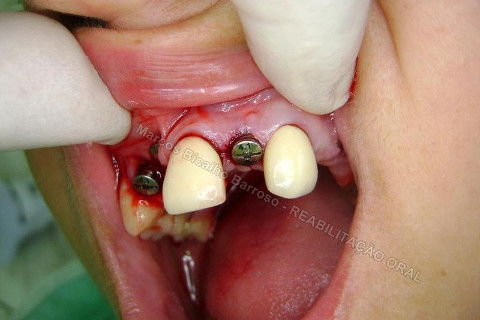

Iniciei esta etapa com o uso de um bisturi circular para contra ângulo. Na verdade, estou postando novamente este procedimento, mas realmente, cheguei depois a conclusão que não deveria ter agido assim nos dentes anteriores, onde a estética é primordial, não devemos remover tecido mole, mas manipular para promover um aumento de papila. Este bisturi é útil para dentes posteriores, adianta bastante o trabalho, é rápido, remove uma porção do formato e dimensão da plataforma do implante, a conta para adaptação do cicatrizador.

Reparem no corte...bonitinho mas fiquei com raiva depois. rsrsrs. Caramba, por que que eu tinha que tirar esta gengiva dali? Era só enrolar o excesso para a vestibular e conseguiria um bom aumento de volume gengival, o que ajudaria bastante na estética periimplantar. Mas tudo bem, vou fazer a cirurgia periodontal depois para corrigir isto sem cobrar da paciente, só de raiva. hehehe. Tem que rir para não chorar.